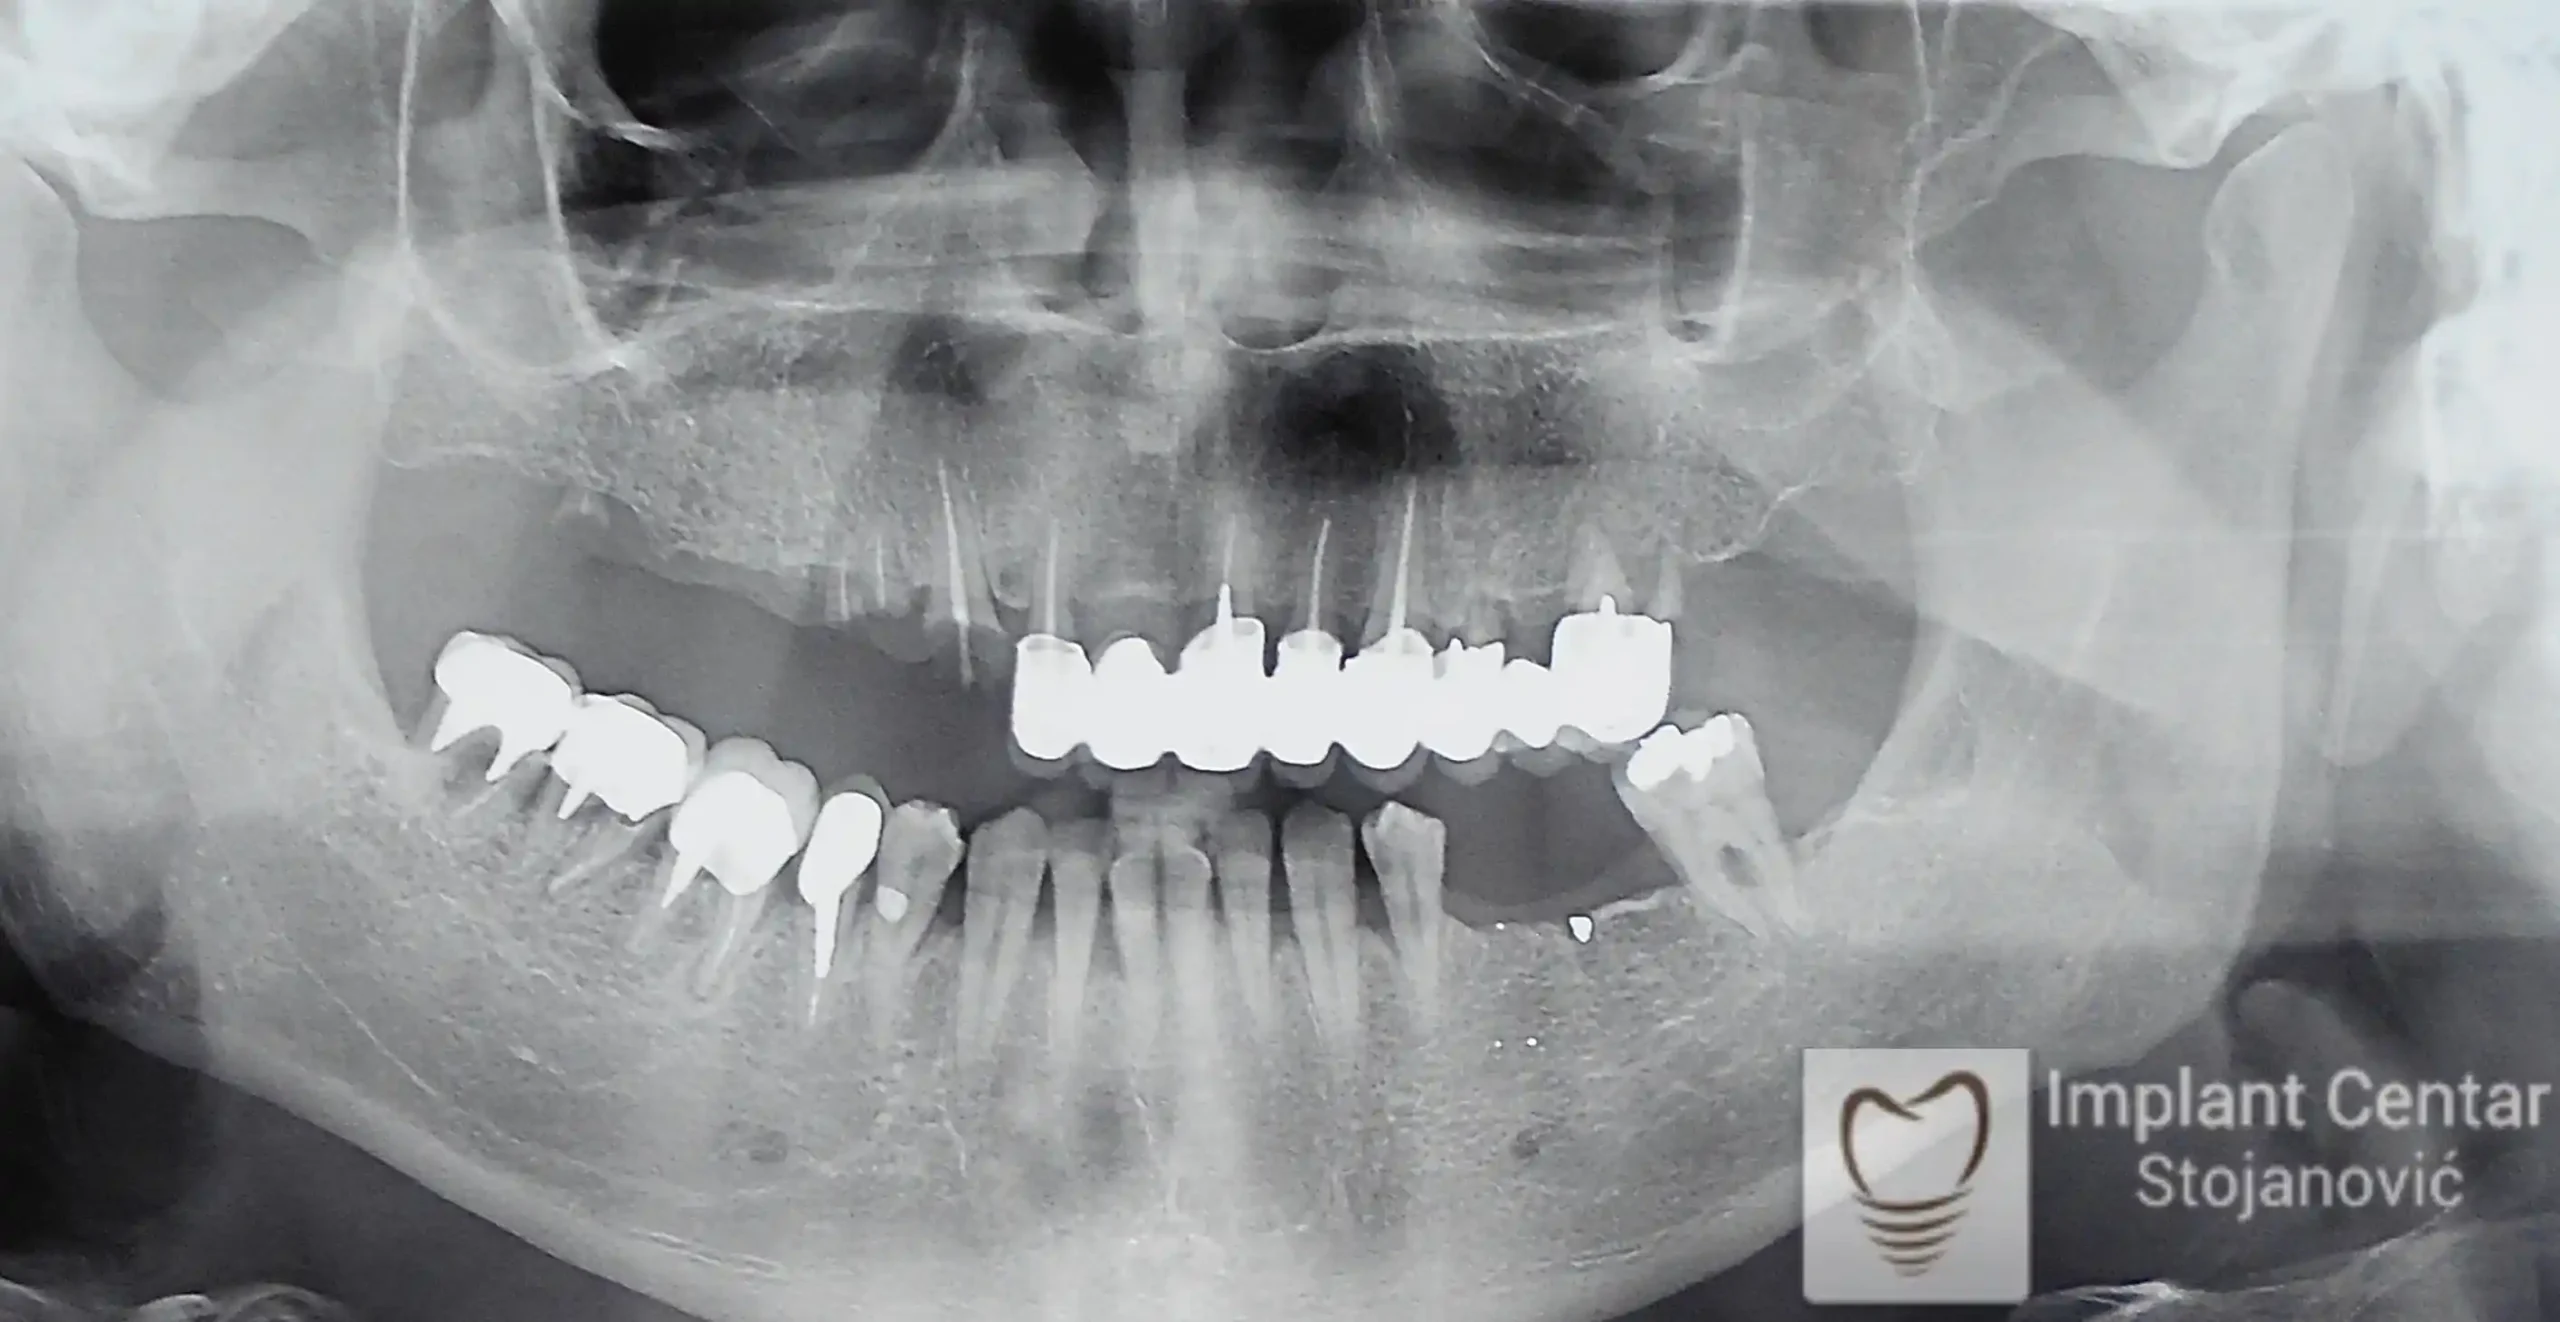

Pacijent sa rascepom usne, nepca i alveolarnog grebena uspešno je rehabilitovan fiksnim protetskim radom na implantatima. Pre dolaska u našu ordinaciju, pacijent je u gornjoj vilici nosio totalnu protezu preko preostalih zuba, dok je u donjoj vilici bio zbrinut parcijalnom mobilnom protezom. Tokom višegodišnje potrage za adekvatnim rešenjem, pacijent nije uspeo da pronađe zadovoljavajuću terapijsku opciju ni u zemlji ni u inostranstvu.

Nakon detaljnog kliničkog pregleda i analize radioloških snimaka, izrađen je sveobuhvatan plan terapije sa ciljem uklanjanja mobilnih proteza i postizanja maksimalne funkcionalne i estetske rehabilitacije. Zbog loše biološke vrednosti preostalih zuba, doneta je odluka o njihovom vađenju i ugradnji dentalnih implantata.

Poseban terapijski izazov predstavljalo je premošćavanje defekta nastalog usled rascepa, kao i ograničena količina raspoložive kosti u gornjoj vilici. Primenom većeg broja implantata i odgovarajućih procedura nadoknade kosti, postignuta je stabilna osnova za fiksni protetski rad.

Tokom perioda oseointegracije, pacijent je bio zbrinut fiksnim privremenim krunicama, čime je već pet dana nakon intervencije obezbeđena potpuna funkcionalna i estetska rehabilitacija. Nakon završetka perioda integracije implantata, izrađeni su definitivni cirkonijum-keramički mostovi na implantatima.